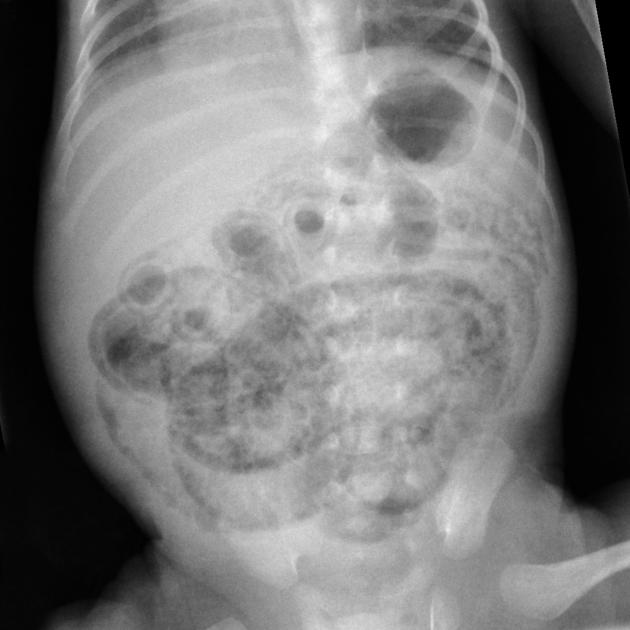

La enterocolitis necrosante (NEC) es una condición grave en neonatos, especialmente en aquellos prematuros, y la ecografía abdominal se ha convertido en una herramienta valiosa para su diagnóstico y manejo. Los hallazgos ecográficos en neonatos con NEC incluyen una serie de características que pueden ayudar a identificar la gravedad de la enfermedad y la necesidad de intervención quirúrgica.

1. Neumatosis intestinal: La presencia de gas en la pared intestinal es un hallazgo clásico y altamente sugestivo de NEC.

2. Neumoperitoneo: La presencia de gas libre en la cavidad peritoneal sugiere perforación intestinal y es una indicación para intervención quirúrgica.[1][3-4]